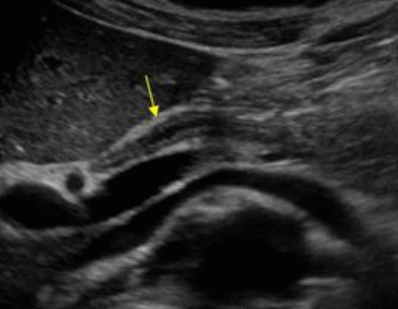

US finding

- 간내담관은 확장되고 간외담관은 정상이다.

- 담낭은 위축되며, 간외담관은 담즙 흐름이 없는 담관으로 묘출된다.

- 폐쇄된 담관부위에 종양의 윤곽이 보일 수 있으나 초음파상 발견하기 어렵다.